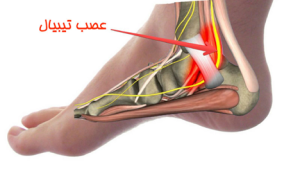

تونل تارسال یک گذرگاه باریک در زیر سطح داخلی مچ پا و در مجاورت استخوانهای آن است. این گذرگاه توسط یک رباط ضخیم پوشانده شده است که از ساختارهای تونل (برخی عصبها یا عروق داخلی ) محافظت کرده و آنها را حفظ می کند. (تصویر شماره ۱)

سندروم تونل تارسال زمانی به وجود میآید که علائم و نشانههای مختلفی در قسمت پا به وجود آمده باشد که ناشی از فشار بر عصبی به نام تیبیال در پشت قوزک داخلی مچ پا هستند. این سندروم در قوزک پا شباهت زیادی به سندروم تونل کارپال در قسمت مچ دست دارد.(تصویر شماره ۲)

سندرم تونل تارسال یک عارضهی دردناک است که کف پا را درگیر کرده و علت ایجاد آن، فشار بر روی عصب تیبیال خلفی است که از درون تونل تارسال میگذرد.

تصویر شماره ۱: تونل تارسال

تصویر شماره ۲، عصب تیبیال و مسیر عبور آن از تونل تارسال